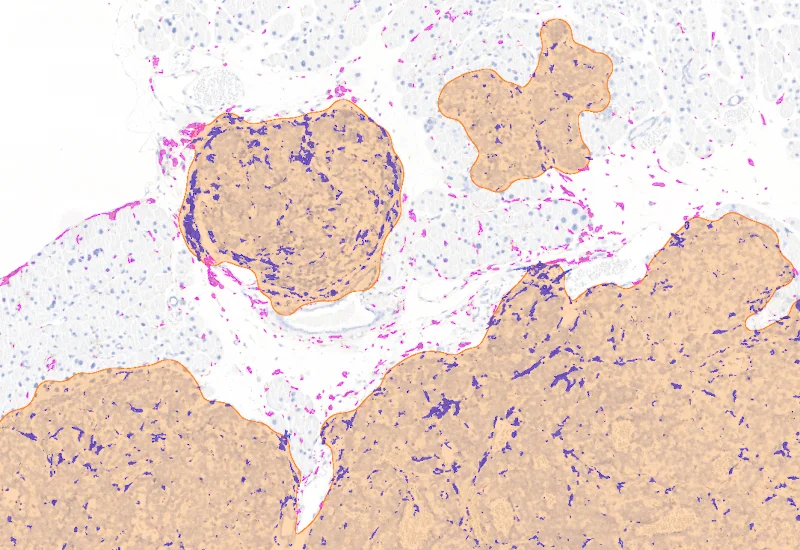

The Tumor Foci App allows to detect the whole tissue and more important tumor foci based on nuclear structure analysis, mainly on HE staining. The number and area of tumor foci as well as their density is measured.

Tumor foci detection